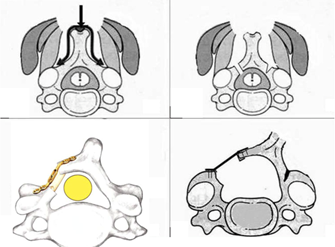

Figura 1: Procedimiento quirúrgico: disección, osteotomías y estabilización con mini placas, tornillos lamino articulares

Se realiza la osteotomía completa con fresa a nivel de la unión de las láminas con los macizos articulares del lado a abrir, Una vez realizada la osteotomía se procede al lado contralateral, realizando una osteotomía incompleta con fresa, logrando una bisagra con cierta capacidad de ceder. Se completa la osteotomía con Kerrison de 1 o 2 mm. Se realizó la osteotomía del lado que presentaba elementos radiculares, de no tenerlos quedaba a criterio del cirujano (a izquierda) Figura 2.

Una vez lograda una apertura satisfactoria se procede a la estabilización con osteosíntesis. Utilizamos mini placas Martin de titanio con tornillos laminoarticulares (5 a 9 mm de longitud) Figura 3.

En la Figura 4 vemos el esquema de la técnica original, empleada por nosotros, Mostramos la imagenología de uno de nuestros casos clínicos con una canal estrecho cervical destacado en la RMN de la Figura 5, y la Rx posoperatorio en la Figura 6.

Figura 4: Esquema sobre la técnica deO'Brien et al.para laminoplastia cervical expansiva. A. Tiempo óseo con corte de las láminas. B. Apertura lateral (open door). C. Estabilización con miniplacas